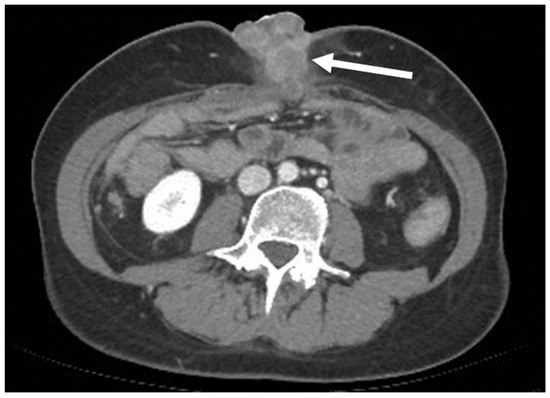

- Desmoplastic Small Round Cell Tumor (DSRCT): rare, highly aggressive sarcoma of adolescents, which primarily involves the serosal surfaces of the abdominal cavity infiltrating the abdominal wall [30,31,32]. Classic findings include bulky multiple, hypoattenuating, soft-tissue masses, with omental, serosal, and rectovesical involvement [31,32] and typical punctate or amorphous calcifications [32]. Modest heterogeneous enhancement is seen on arterial phase, without prolonged enhancement or portal washout [31,32] (Figure 10). On MR, DSRCTs are heterogeneously iso- to-hypointense on T1-w images, with hyperintense foci due to intratumoral hemorrhage [32].